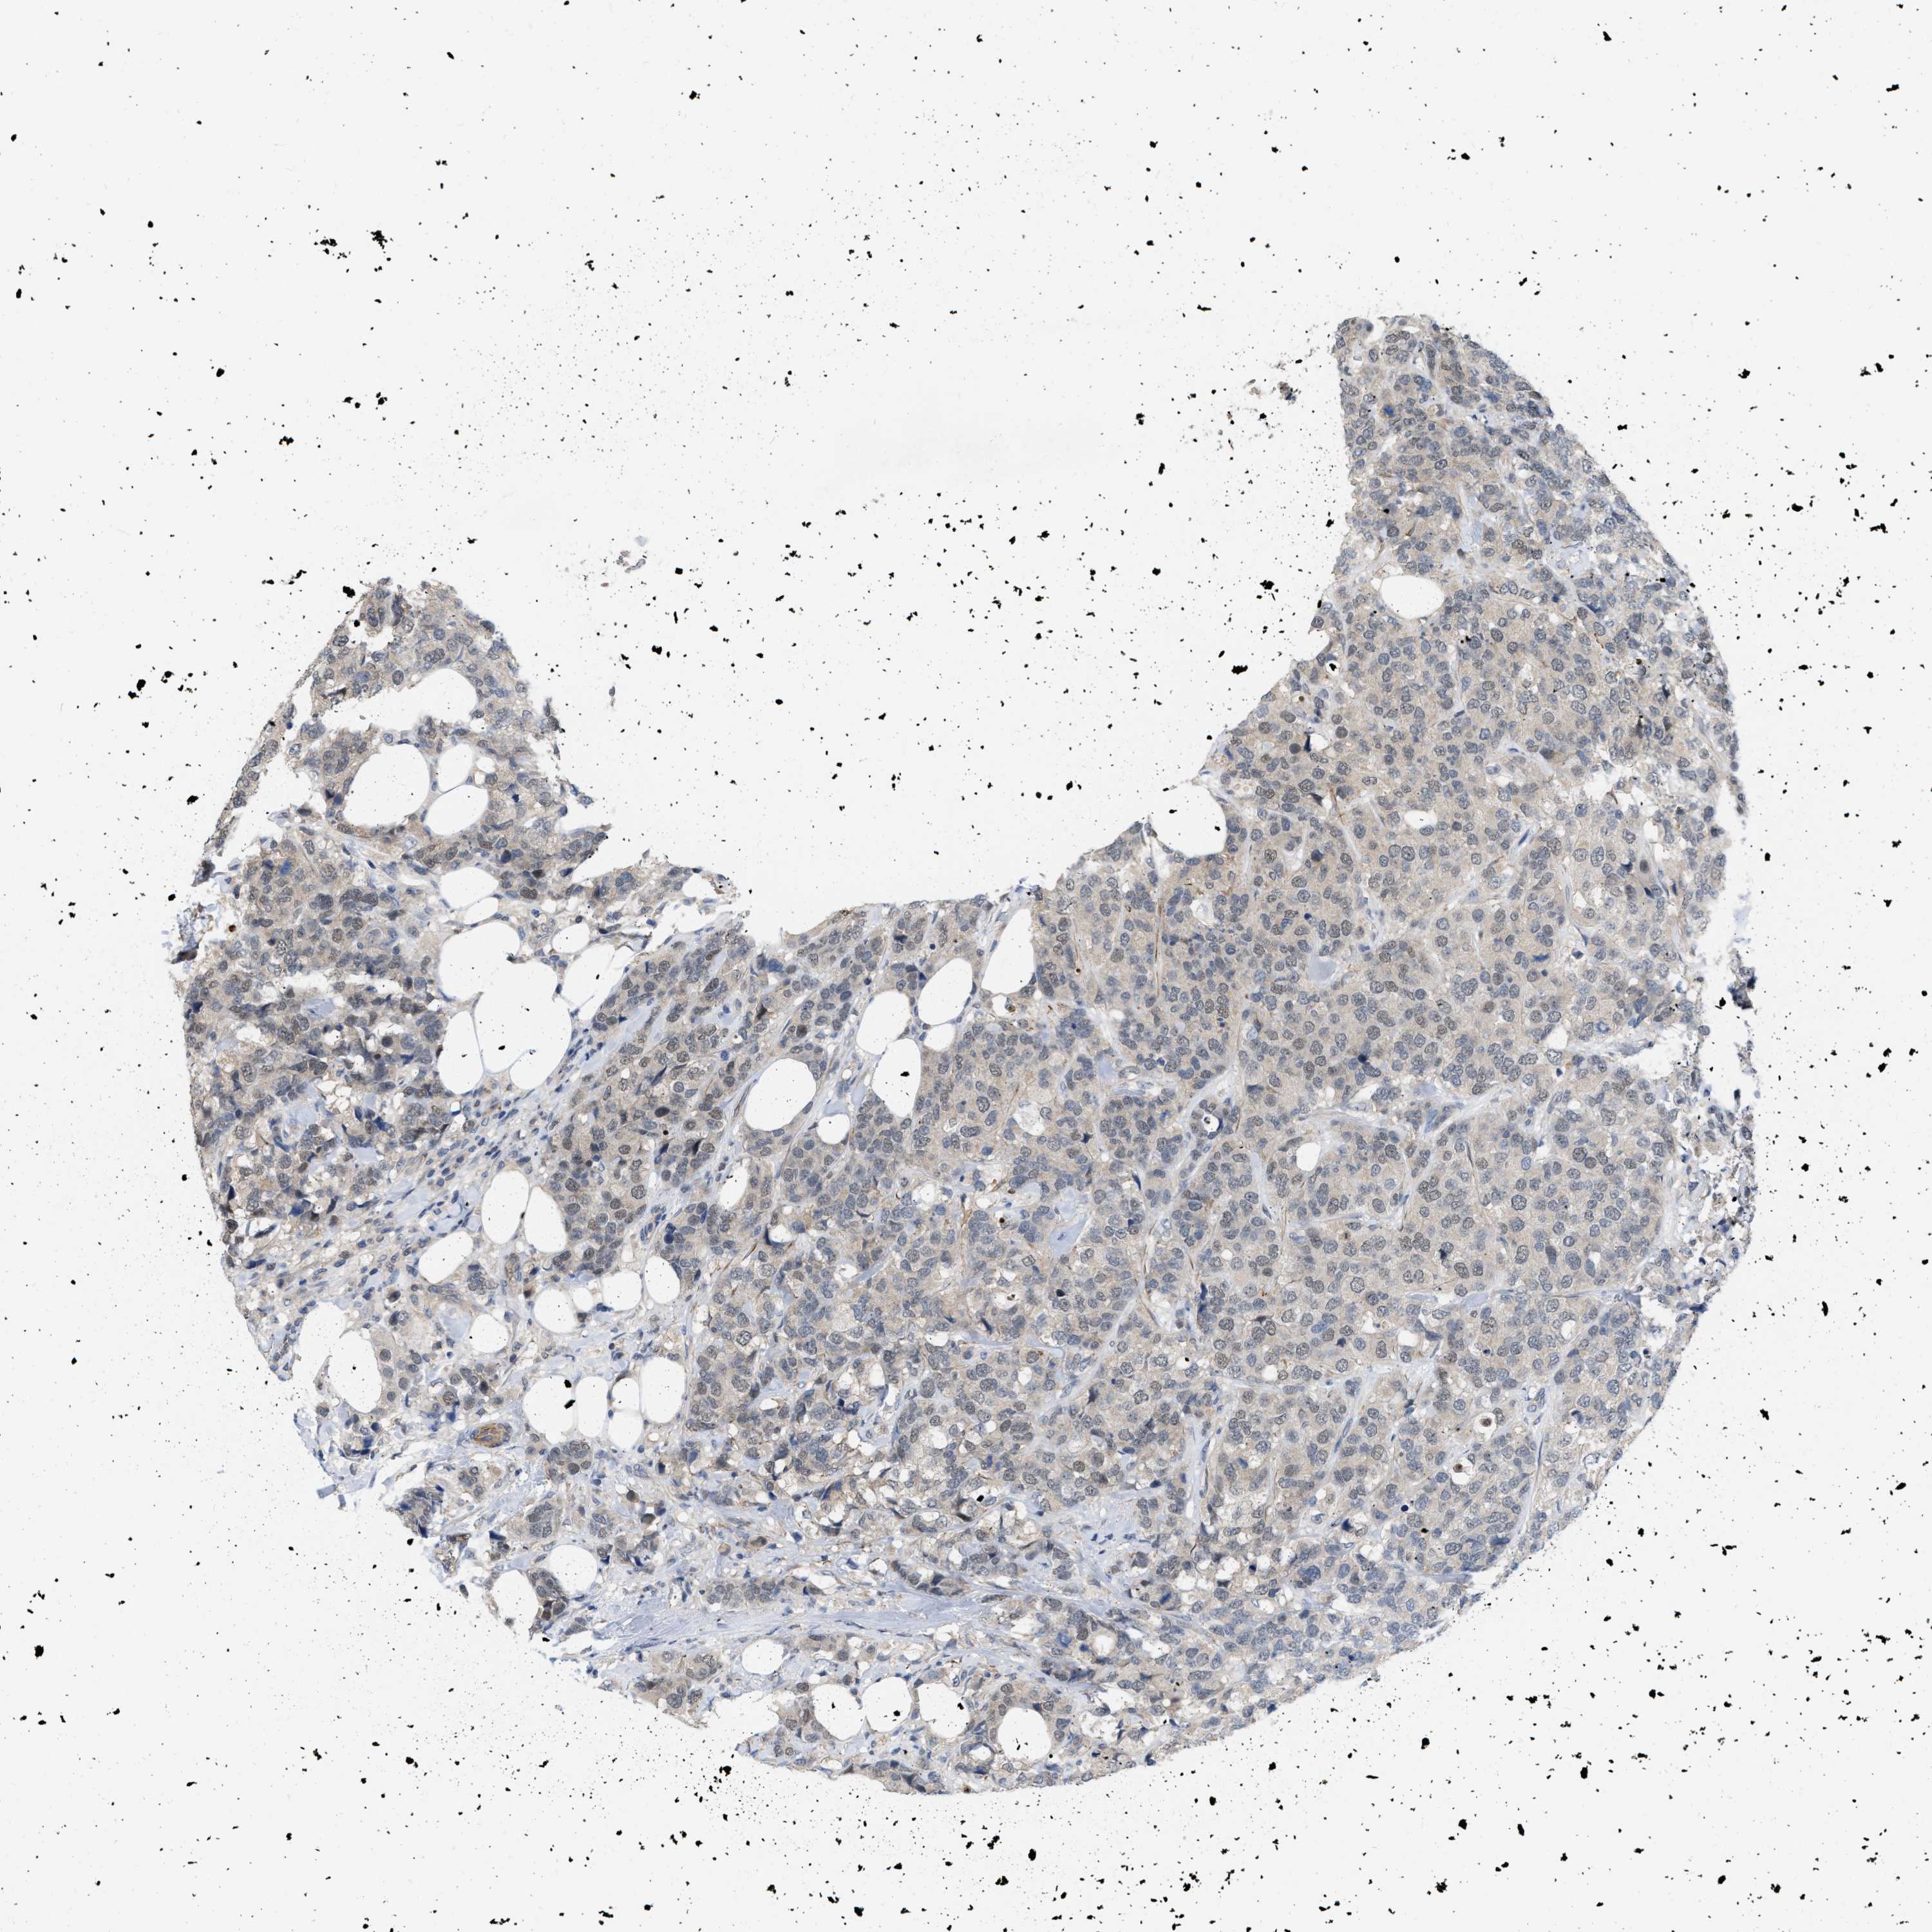

CANCER BREAST CANCER Show tissue menu

BRCA TCGA BRCA VALIDATION PROTEIN EXPRESSION

ANTIBODIES

AND

VALIDATION